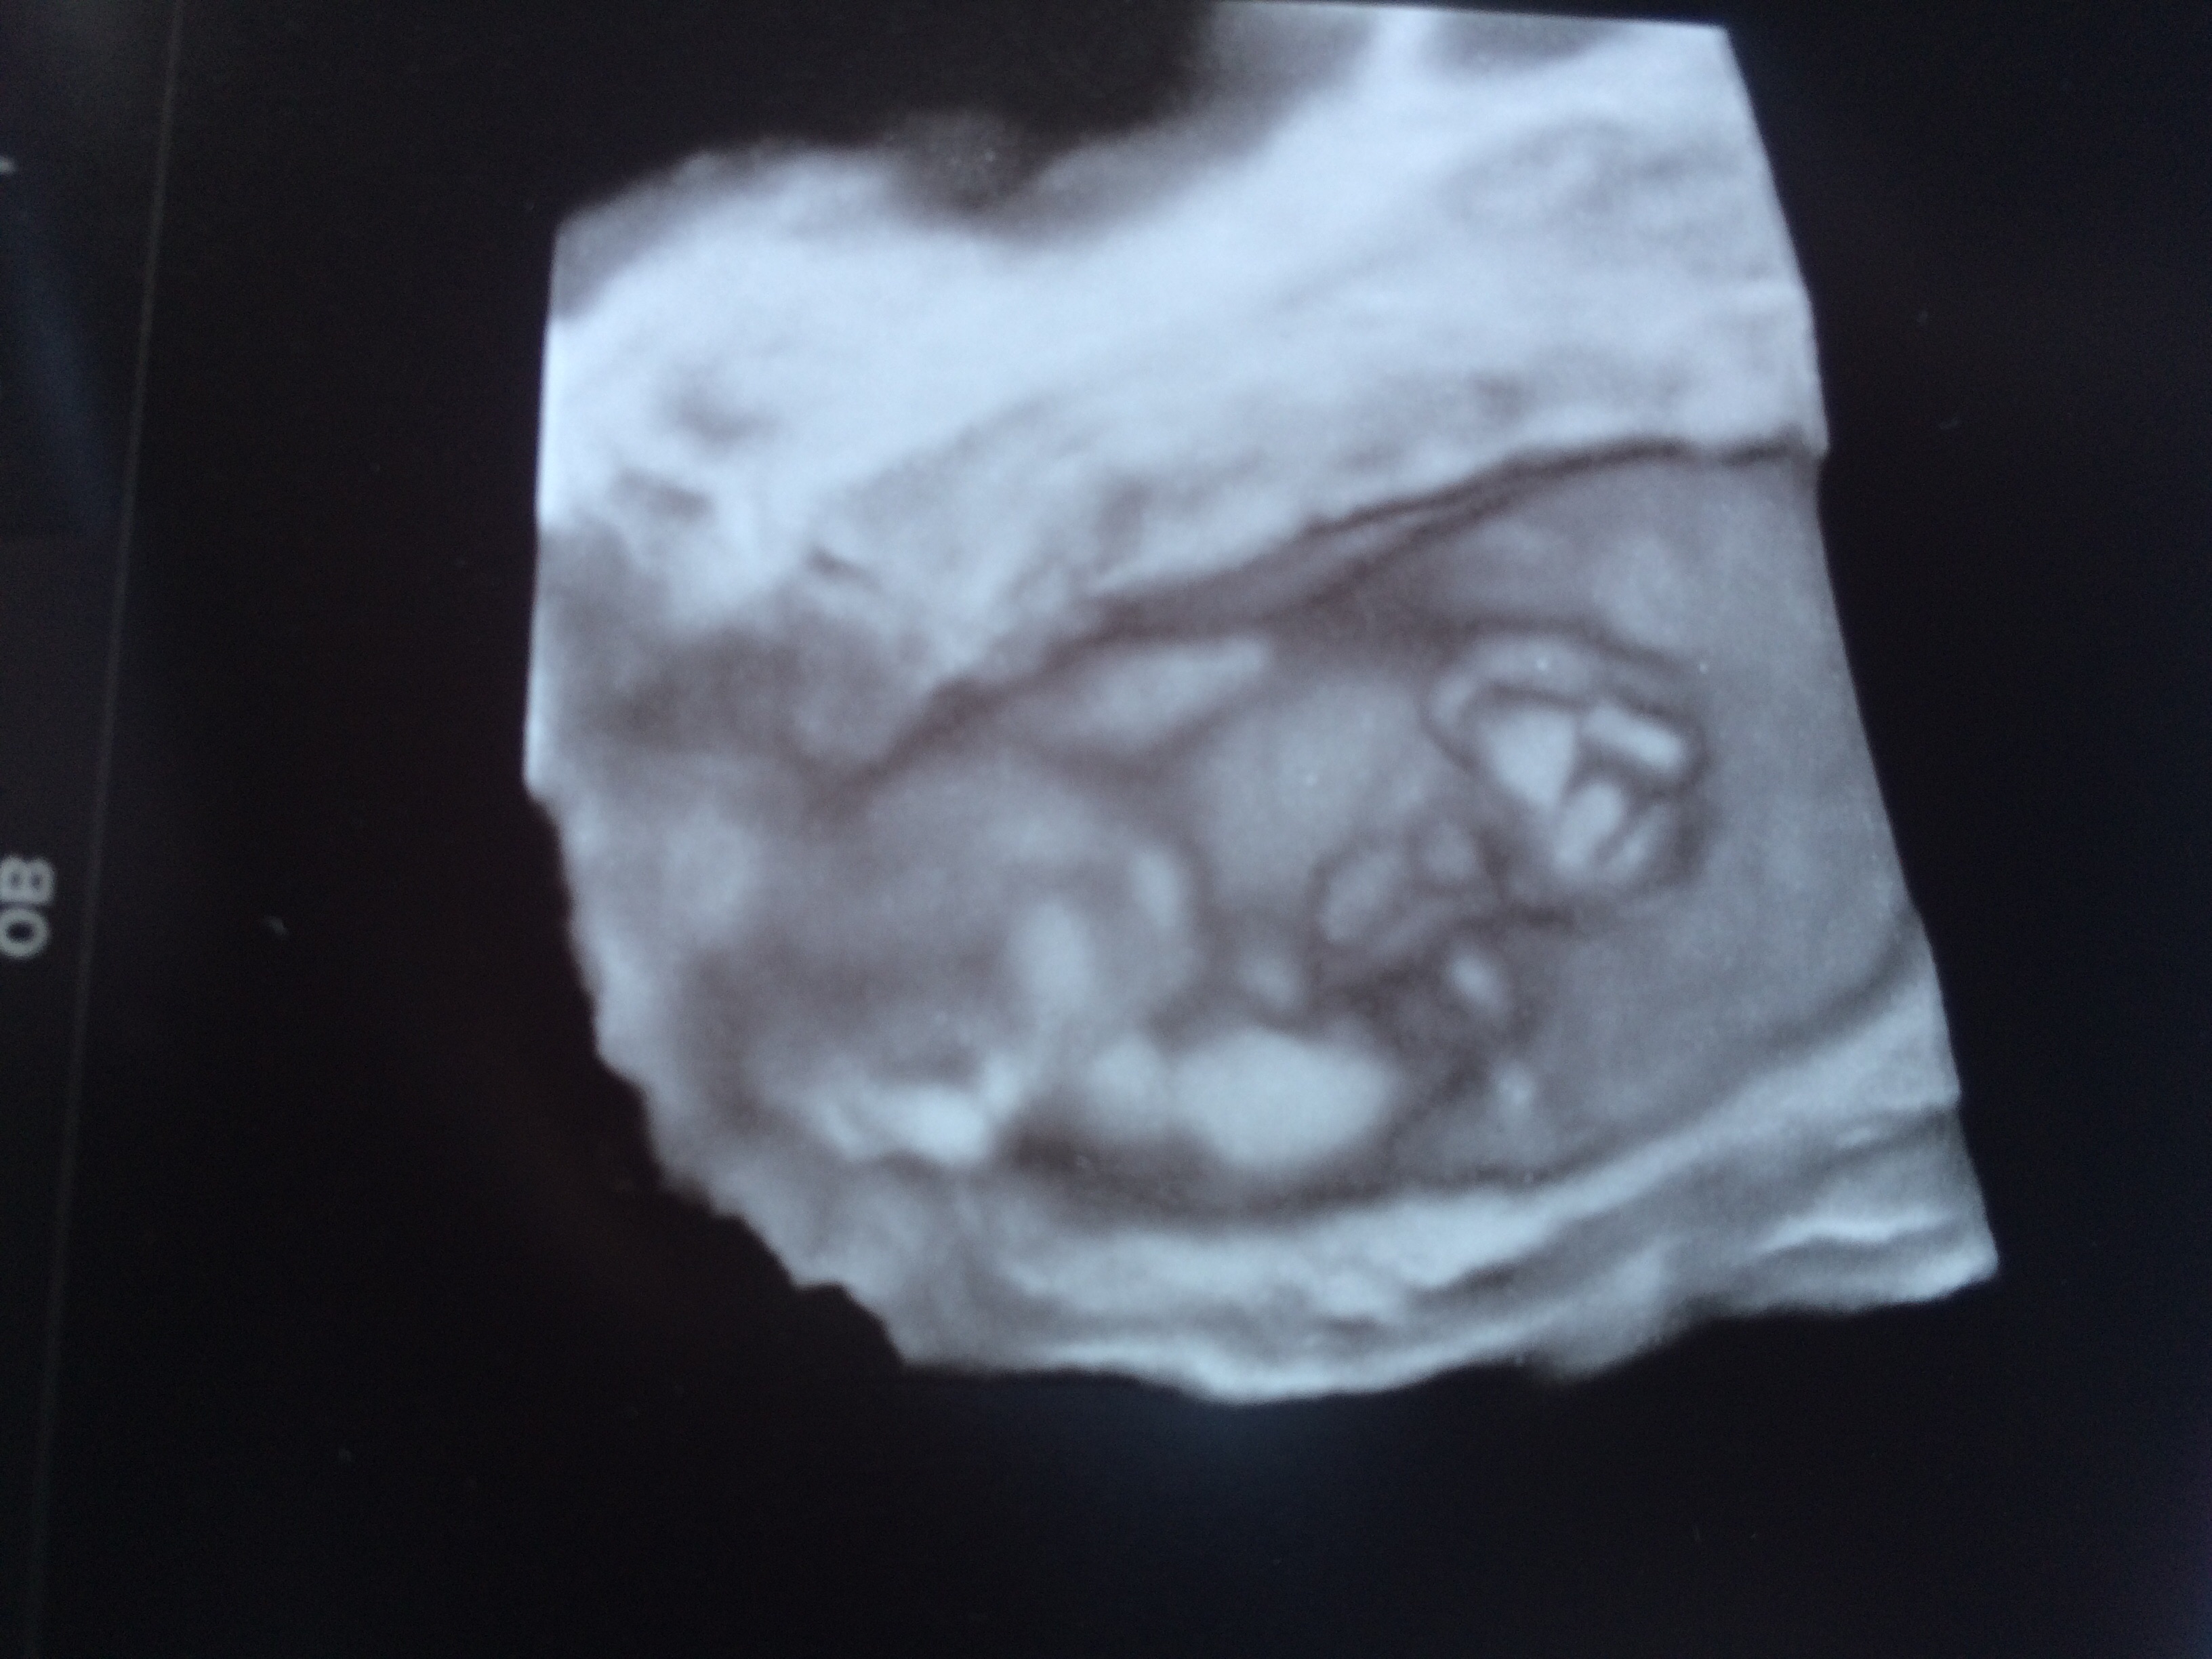

12+5 3D

Guessing boy based on second picture!

Pic 2 shows a boyish looking skull.